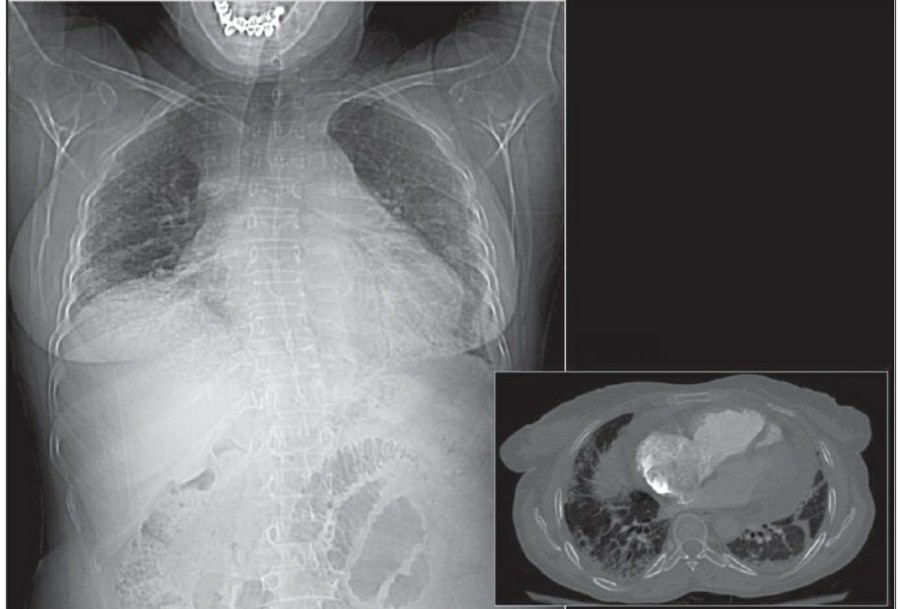

중환자에서 pneumothorax의 진단은 종종 supine radiograph에서 내릴 수 있다. Supine position에서 공기는 anteromedial 방향으로 모이게 되는데, apical air collection이 있을 경우 large pneumothorax가 있음을 시사한다. 공기는 lung과 diaphragm 사이의 subpulmonic location에 trap 되어 있을 수도 있다. 공기가 costophrenic sulcus로 anterolateral extension 될 경우, 이 costophrenic sulcus의 radiolucency를 증가시키는데, 이를 deep sulcus sign이라고 한다. Subpulmonic pneumothorax의 다른 특징으로 diaphragm의 superior surface와 IVC 윗부분이 뚜렷하게 보일 수 있다.

중환자에서 tension pneumothorax의 진단은 매우 힘들다. ARDS와 같은 lung의 병리적인 기전이 lung compliance를 감소시킴으로써 total lumg collapse를 막는다. 또한 tension pneumothorax의 특징인 mediastinal shift가 PEEP으로 인해 나타나지 않을 수 있다. Chest X ray 상에서 tension pneumothorax는 hemidiaphragm의 depression이나 heart border, SVC, IVC의 이동으로 나타날 수 있다.